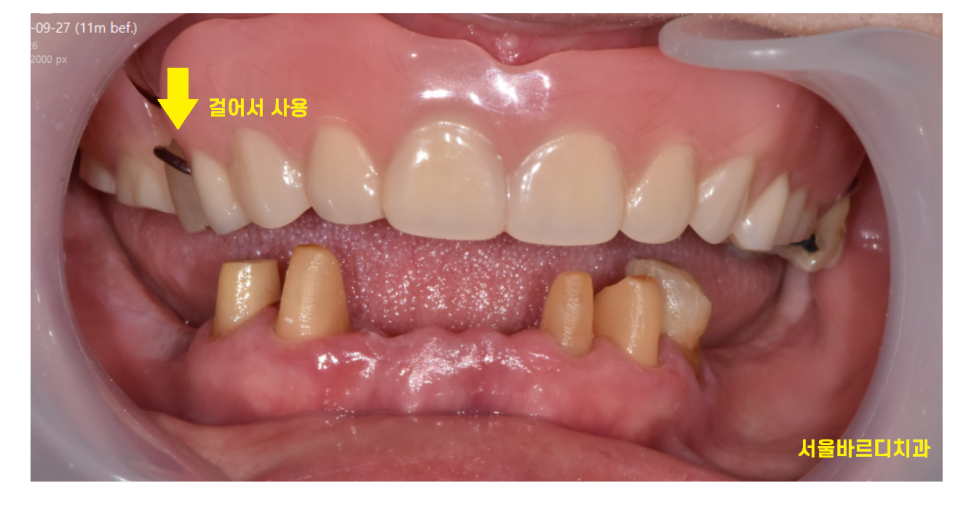

23.09.27

틀니는 잇몸 위에 얹어서 사용하고

양쪽 치아가 상실되었을 때

치료를 진행합니다.

쉽사리 환자분께서 결정을 못하시기에

길동 치과에서는 임시틀니를 한번 사용해보고

결정해보시라고 권유드렸는데요.

23.11.29

임시틀니로 틀니를 사용하는 방법도 익히고

어떤 느낌인지 확인해보시라고

한 부분도 있었죠.